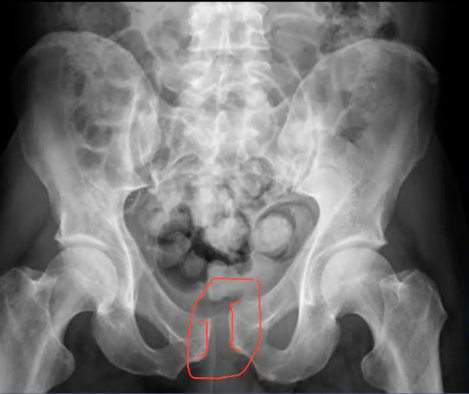

A 30 year old man was thrown from his motorbike at speed. His X-ray is shown.

What do you make of the X-rays? How would you describe the injury? What do think the mechanism of injury was? Any concerns about other structures that could potentially be injured? What would you do next?